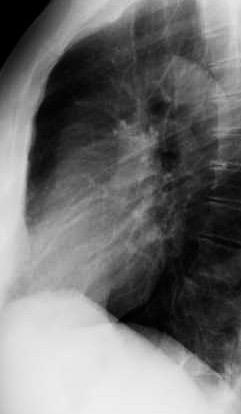

Parálisis frénica transitoria tras cirugía de válvula aórtica

Parálisis frénica transitoria post cirugía cardiaca (10%).

Puede acompañarse de atelectasia del LII.

Benjamin JJ et al. . Left lower lobe atelectasis and consolidation following cardiac surgery: the effect of topical cooling on the phrenic nerve. Radiology 1982